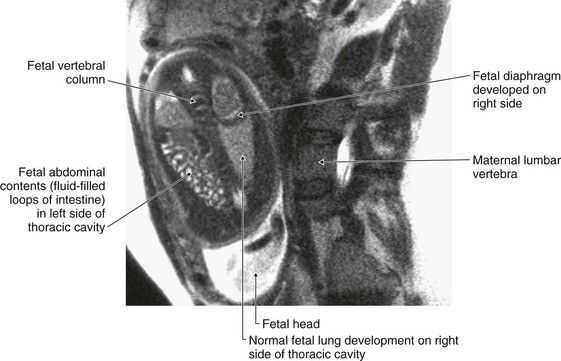

To understand why a hernia occurs through the diaphragm, it is necessary to consider the embryology of the diaphragm.

The diaphragm is formed from four structures—the septum transversum, the posterior esophageal mesentery, the pleuroperitoneal membrane, and the peripheral rim—which eventually fuse together, so separating the abdominal cavity from the thoracic cavity. The septum transversum forms the central tendon, which develops from a mesodermal origin in front of the embryo’s head and then moves to its more adult position during formation of the head fold.

Fusion of the various components of the diaphragm may fail, and hernias may occur through the failed points of fusion (Fig. 4.133). The commonest sites are:

image between the xiphoid process and the costal margins on the right (Morgagni’s hernia); and

image through an opening on the left when the pleuroperitoneal membrane fails to close the pericardioperitoneal canal (Bochdalek’s hernia).

image

Fig. 4.133 Fetal diaphragmatic hernia in utero. T2-weighted MR image. Fetus in coronal plane, mother in sagittal plane.

Hernias may also occur through the central tendon and through a congenitally large esophageal hiatus.

Morgagni’s and Bochdalek’s hernias tend to appear at or around the time of birth or in early infancy. They allow abdominal bowel to enter the thoracic cavity, which may compress the lungs and reduce respiratory function. Most of these hernias require surgical closure of the diaphragmatic defect.